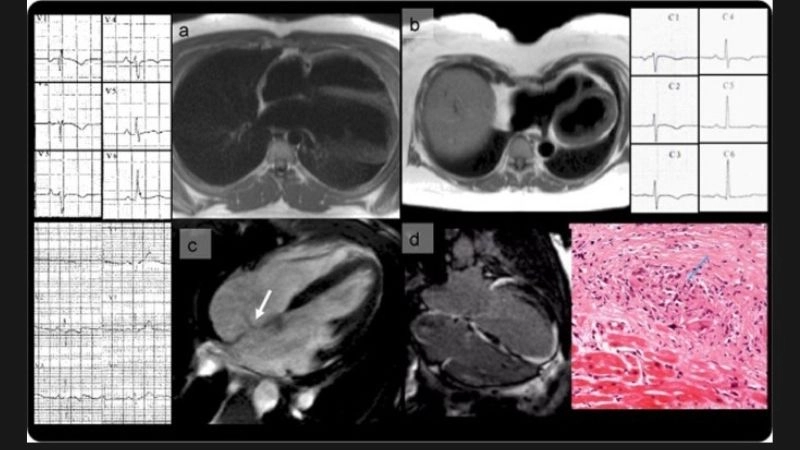

Images visual examples of Arrhythmogenic Right Ventricular Cardiomyopathy (ARVC)

Visual examples often show scarring and structural changes in the heart wall, helping illustrate how the condition disrupts both pumping function and electrical signaling.

Arrhythmogenic Right Ventricular Cardiomyopathy diagnosis uses ECG, MRI, and genetics